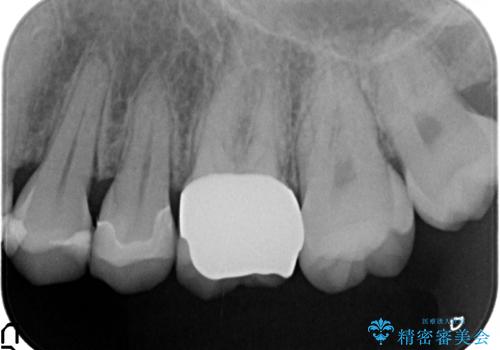

左上6は虫歯を除去後、神経症状がないことを確認し、オールセラミッククラウンによる補綴を行いました。

当院のセラミックインレーはemaxという強度と審美性に優れた材料を使用しています。

またプレス方式でインレーを製作しているため、削り出しで製作するCADCAMより優れた適合性も持ち合わせており、虫歯が再発しにくい修復物です。

今回用いたオールセラミッククラウンはジルコニアフレームという白い素材の上にセラミックを盛っているため、審美性が非常に高いのが特徴です。

また、ジルコニアは人工ダイヤモンドの材料にも使われているほど高い強度を持っており、そのためオールセラミッククラウンは審美性だけでなく、奥歯やブリッジの補綴も可能とするクラウンです。